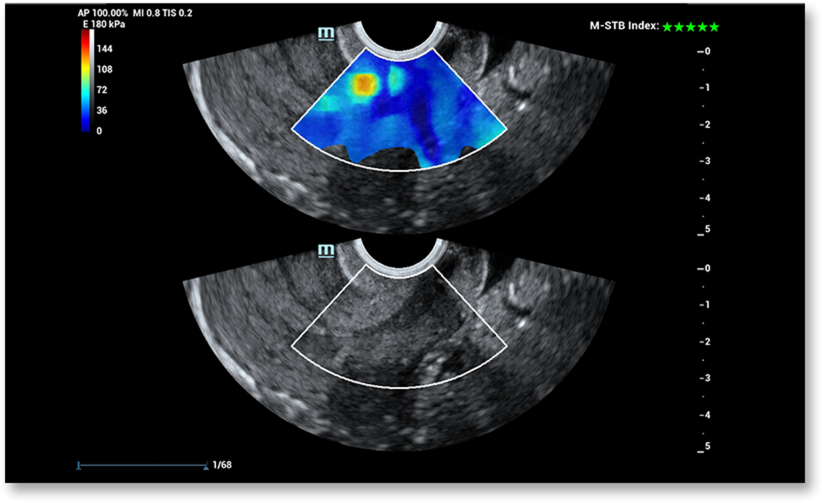

Mindray-ի բացառիկ Ultra-wide Beam Tracking տեխնոլոգիայի շնորհիվ STE համակարգը իրական ժամանակում ապահովում է շիեր ալիքով (shear wave) երկչափ էլաստոգրաֆիա՝ օգտագործելով մասնագիտական չափիչ գործիքներ առաձգականության համալիր քանակական վերլուծության համար։ Միաժամանակ STE-ն օպերատորից անկախ է, ինչը ապահովում է արդյունքների լավ վերարտադրելիություն և առաձգականության քանակական գնահատման բարձր ճշգրտություն։